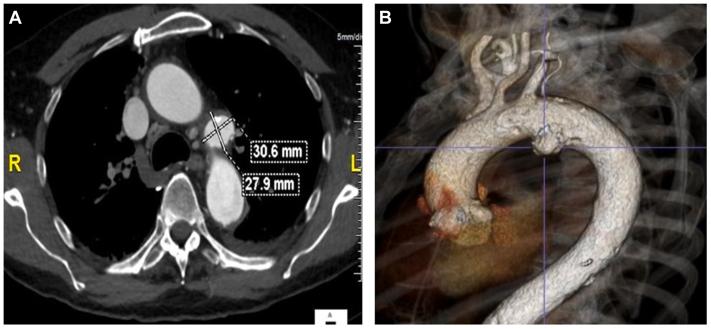

We present the case of a 75-year-old man with a symptomatic penetrating aortic ulcer located in zone 2 on the arch inner curve between the left subclavian artery and left carotid artery treated using a single branch thoracic endovascular aortic repair combined with in situ laser fenestration. The patient underwent a successful procedure with no neurologic impairment and was discharged on the second postoperative day. The postoperative follow-up showed a well-excluded penetrating aortic ulcer.

我们报告一例75岁男性患者,其症状性穿透性主动脉溃疡位于主动脉弓内曲线的2区,介于左锁骨下动脉和左颈动脉之间,采用单分支胸主动脉腔内修复术联合原位激光开窗术进行治疗。患者手术成功,无神经功能损害,术后第二天出院。术后随访显示穿透性主动脉溃疡得到良好封堵。